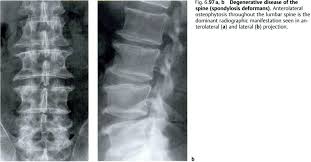

Bone And Joint Disorders Degenerative Disease Bone And Joint Medical Imaging